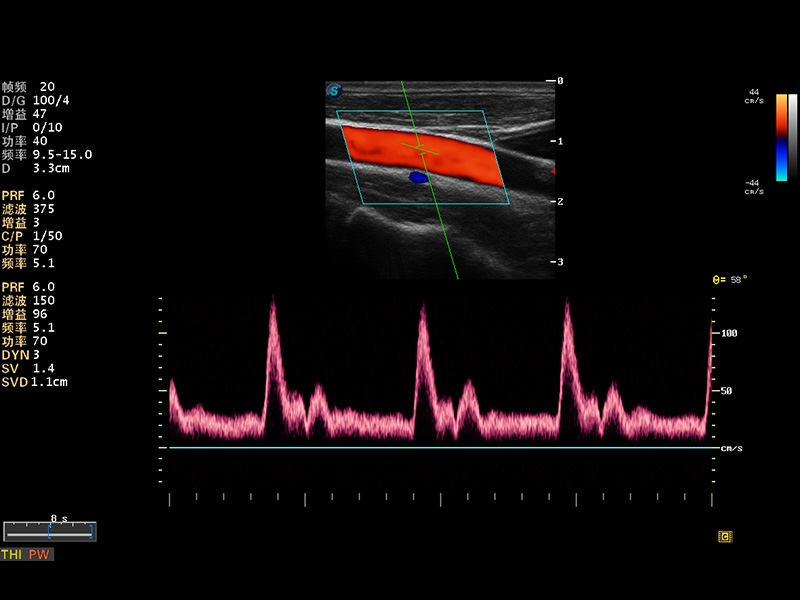

S8 EXP便携式彩色多普勒超声诊断仪是milan米兰研发的高端全身应用型便携彩超。高通道的VIS平台融合可视化(Visual)、智能化(Intelligent)和人性化(Smart)的特点,配以milan米兰自主研发生产的探头大家族,使您能够快速、准确的获得病人信息,提高工作效率的同时减轻疲劳。

μ-Scan微米成像

谐波成像